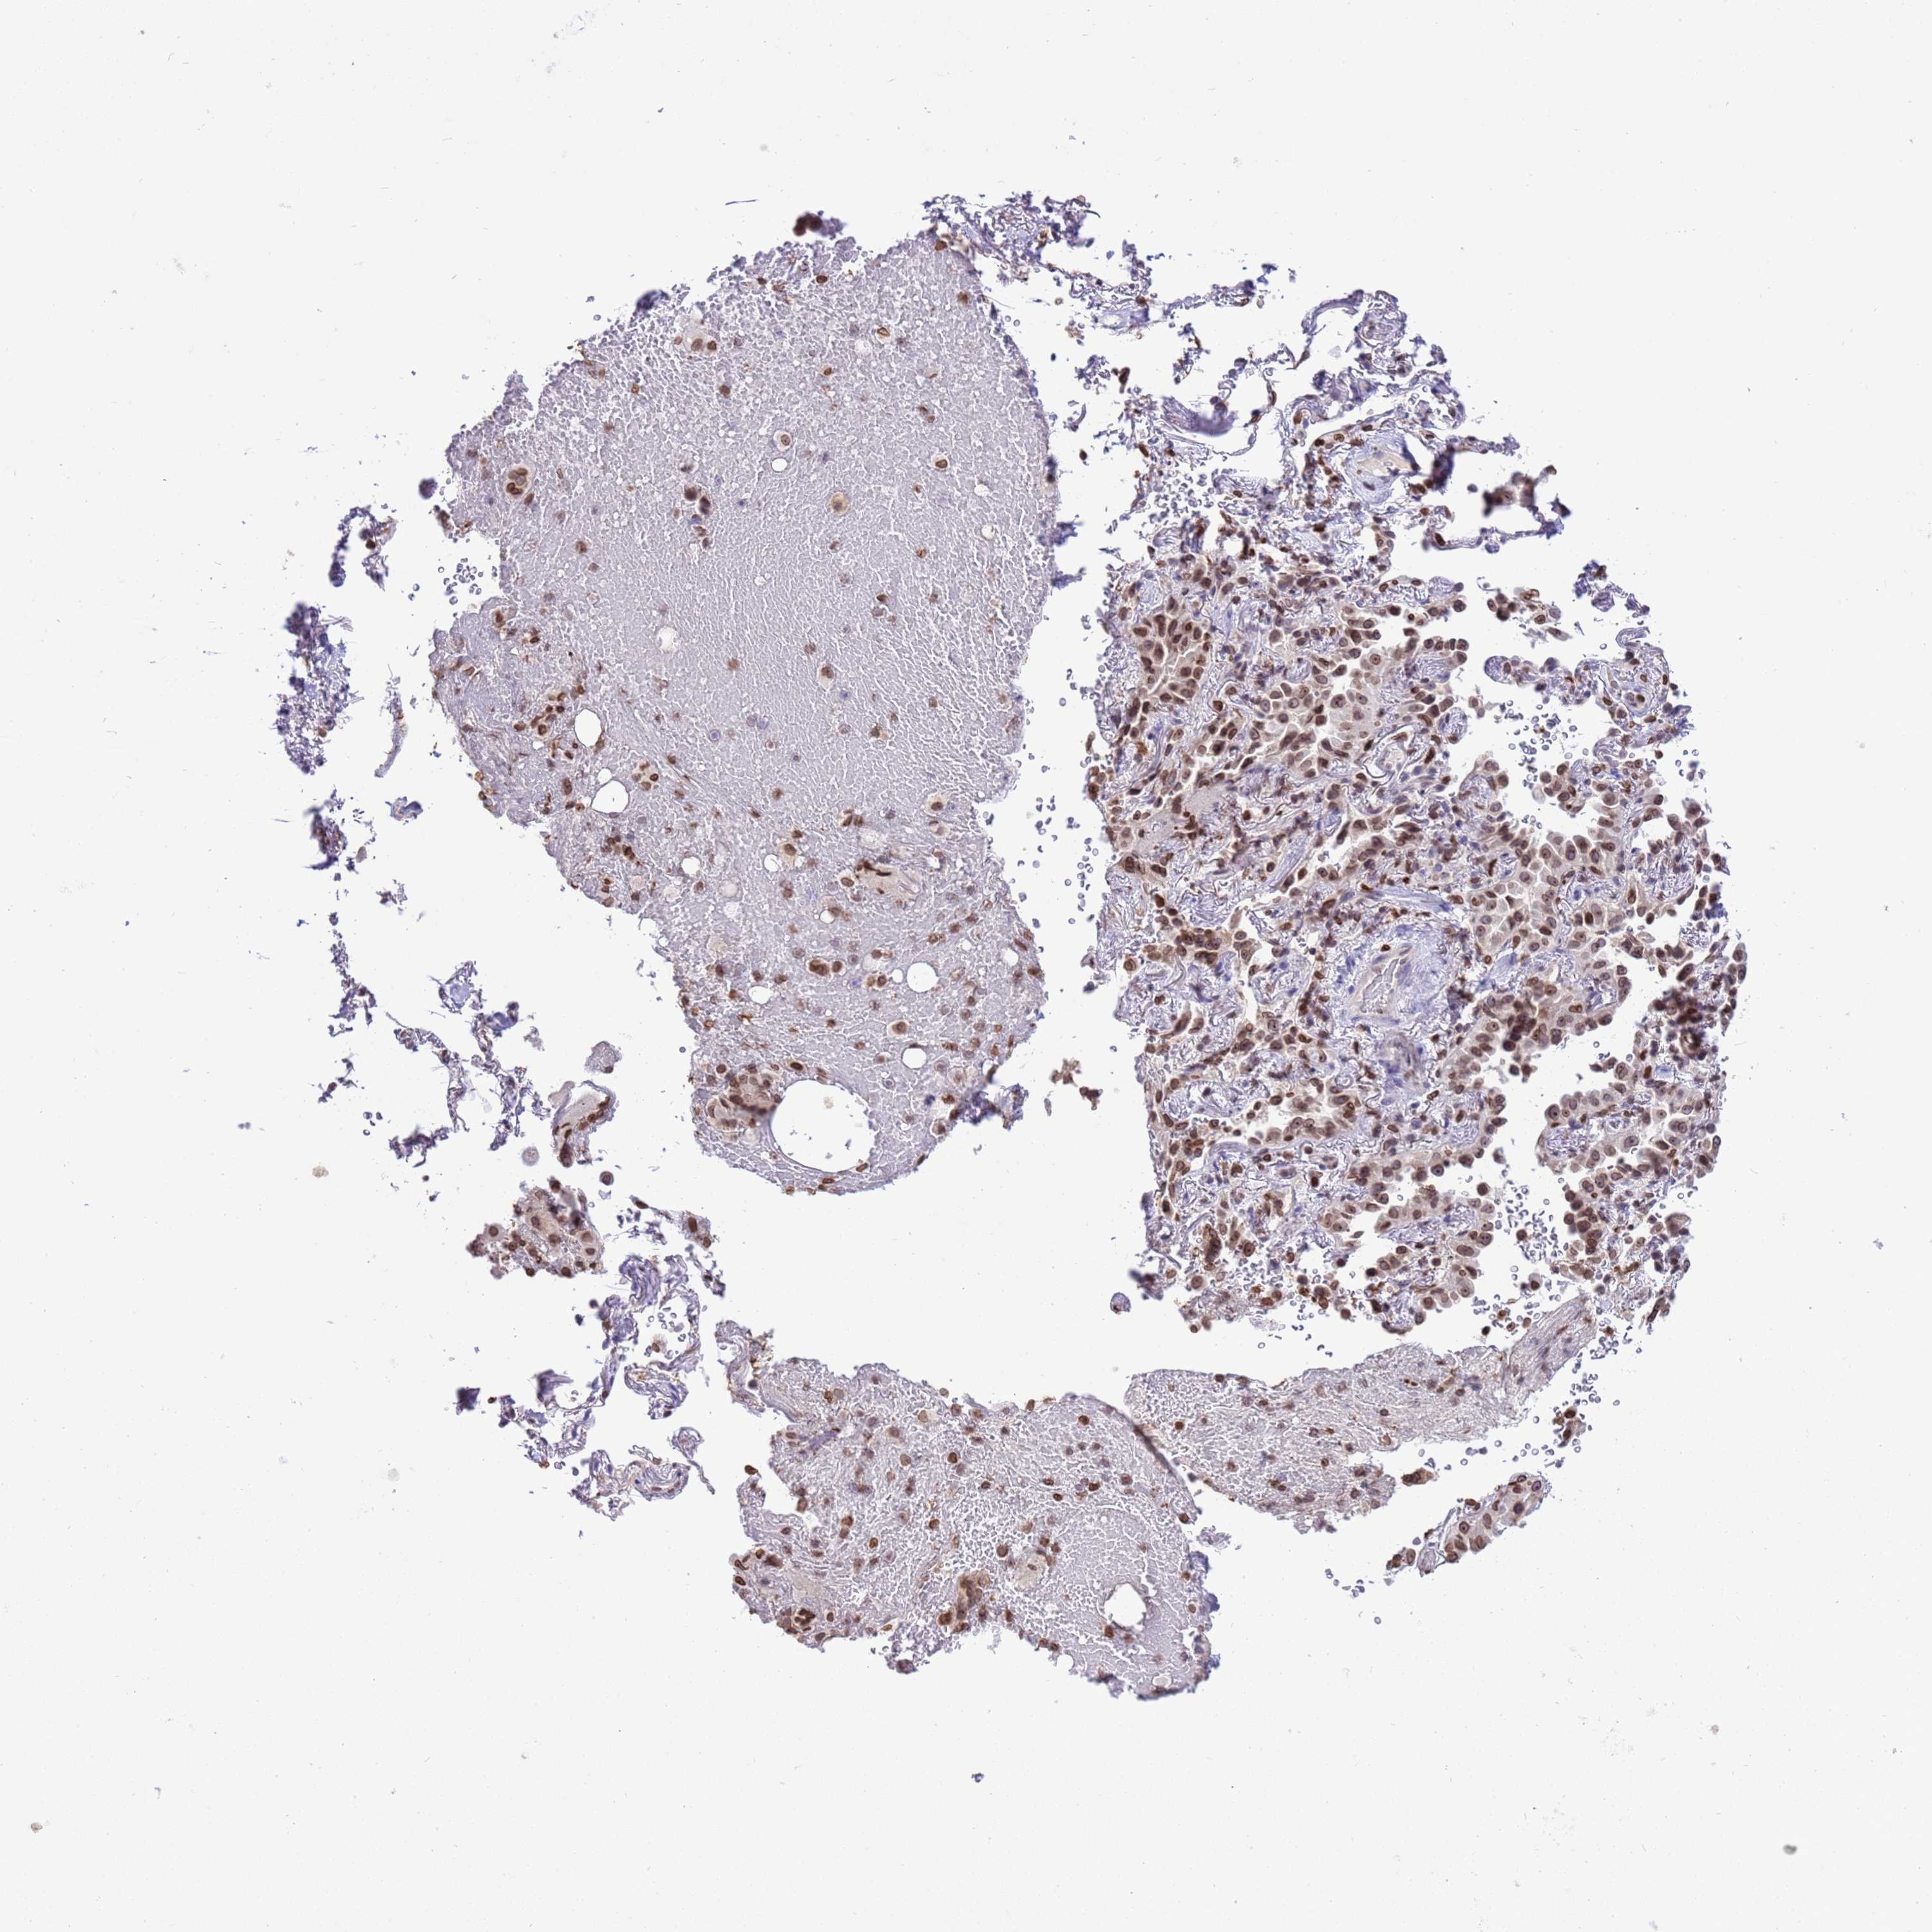

LUNG ADENOCARCINOMA (VALIDATION) - Interactive survival scatter ploti

The Survival Scatter plot shows the clinical status (i.e. dead or alive) for all individuals in the patient cohort, based on the same data that underlies the corresponding Kaplan-Meier plots. Patients that are alive at last time for follow-up are shown in blue and patients who have died during the study are shown in red.

The x-axis shows the expression levels (FPKM) of the investigated gene in the tumor tissue at the time of diagnosis. The y-axis shows the follow-up time after diagnosis (years). Both axes are complimented with kernel density curves demonstrating the data density over the axes. The top density plot shows the expression levels (FPKM) distribution among dead (red) and alive patients (blue). The right density plot shows the data density of the survived years of dead patients with high and low expression levels respectively, stratified using the cutoff indicated by the vertical dashed line through the Survival Scatter plot. This cutoff is automatically defined based on the FPKM cutoff that minimizes the p-score. The cutoff can be changed by dragging the vertical line or by entering a cutoff value in the square labeled "Current cut-off".

Under the Survival Scatter plot the p-score landscape (black curve; left axis) is shown together with dead median separation (red curve; right axis). Dead median separation is the difference in median mRNA expression between patients who have died with high and low expression, respectively. It is calculated as follows: median FPKM expression of dead patients with high expression - median FPKM expression of dead patients with low expression. This is intended to aid the user in visually exploring custom cutoffs and the associated p-scores and dead median separation.

Individual patient data is displayed and can be filtered by clicking on one or more of the category buttons on the top of the page. Categories describing expression level and patient information include: high, low, alive, dead, female, male and tumor stages. The scale of the x-axis can be toggled between linear and log-scale by clicking on the "x log" button. Mouse-over function shows TCGA ID, patient information and mRNA expression (FPKM) for each patient.

& Survival analysisi

Kaplan-Meier plots summarize results from analysis of correlation between mRNA expression level and patient survival. Patients were divided based on level of expression into one of the two groups "low" (under cut off) or "high" (over cut off). X-axis shows time for survival (years) and y-axis shows the probability of survival, where 1.0 corresponds to 100 percent.

DHX37 is not prognostic in Lung Adenocarcinoma (validation)

: 2.62

Average pTPM 3.0

Number of samples 105